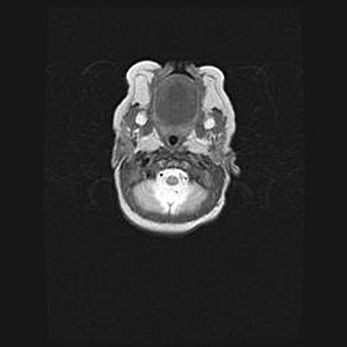

Неполная лизэнцефалия (пахигирия). Открытая гидроцефалия.

Возраст: 17 дней

Вес: 3110 г

Пол: мужской

Окружность головы: 33,5 см

Срок гестации: 35-36 недель

Лизэнцефалия—недоразвитие корковой пластинки и мозговых извилин в результате нарушения миграции нейронов коры. Поверхность мозговых полушарий гладкая. Микроскопически выявляется отсутствие нормальных слоев коры и скопление групп нейронов в подкорковом белом веществе.

Пахигирия—уменьшение числа вторичных извилин. В пораженном полушарии нервные клетки образуют толстый недифференцированный слой с неправильно расположенными нервными волокнами и группами гетеротопных клеток. Нервные клетки незрелые. Белое вещество истончено. При этом нередко аномально развит корково-спинномозговой путь.